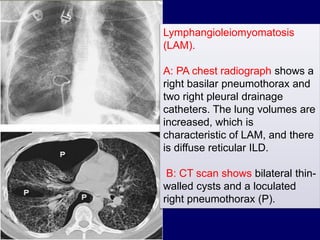

Lymphangioleiomyomatosis

(LAM).

A: PA chest radiograph shows a

right basilar pneumothorax and

two right pleural drainage

catheters. The lung volumes are

increased, which is

characteristic of LAM, and there

is diffuse reticular ILD.

B: CT scan shows bilateral thin-

walled cysts and a loculated

right pneumothorax (P).